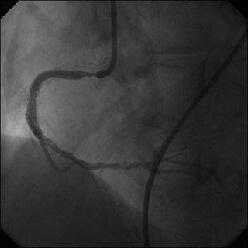

����ALCx take off lesion ��PCI���s���܂����B

�����搶�̌䏕����q�����ċ}篁A�a�i�����搶�j�ɗ���ŗ��Ē����܂����B

CBA(3.5?)+STENT(3.5�~13?)��strategy�ōs������ɂ��Ă��܂������A

�����ő��Z������܂����B

�ƂĂ����p���������̂ł����A�O���ɂق��̐搶��CB(3.5?)���g�p���ꂽ�̂�c��

���Ă��炸�A

�h��������3.5?�o���āI�h�ƌ�������A�h����g�������炠��܂���I�h�Ƃ���

�������Ԃ��Ă��܂����B

��������Stormer(3.5�~15?)��pre������STENT����悤�Ǝv������pre��distal����

�ɑ傫���Ă��܂��A���ǂ����̒ʂ�S670(3.5�~24?)������H�ڂɂȂĂ���

���܂����BCB�������炱��ȂɗȂ����������Ȃ��`�Ƃւ���ł��܂��܂����B

���҂���A�a�A�����Ă��������A�h�o�C�X�����������搶���A�\����܂���B

���x����͑O���ɂ������device�Ƀ`�F�b�N������悤�ɂ��܂��B

�ꉞ�A���ʂ�Y�t���܂��B